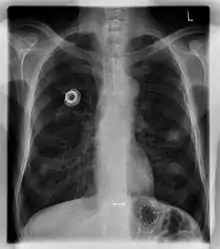

Порт-система — медицинское устройство, предназначенное для введения препаратов, дренирования, забора крови и т. д. Состоит из катетера, помещенного в сосуд или полость, и соединенного с ним резервуара. Вся система располагается подкожно и обеспечивает постоянный венозный, артериальный, перитонеальный, спинальный или плевральный доступ. Для инъекций используется исключительно игла Губера с особой формой острия, которая не повреждает порт.[1]

Главными компонентами порт-системы являются: порт, состоящий из основного корпуса, силиконовой мембраны и обычно титанового резервуара, который подключается к катетеру при помощи канюли.